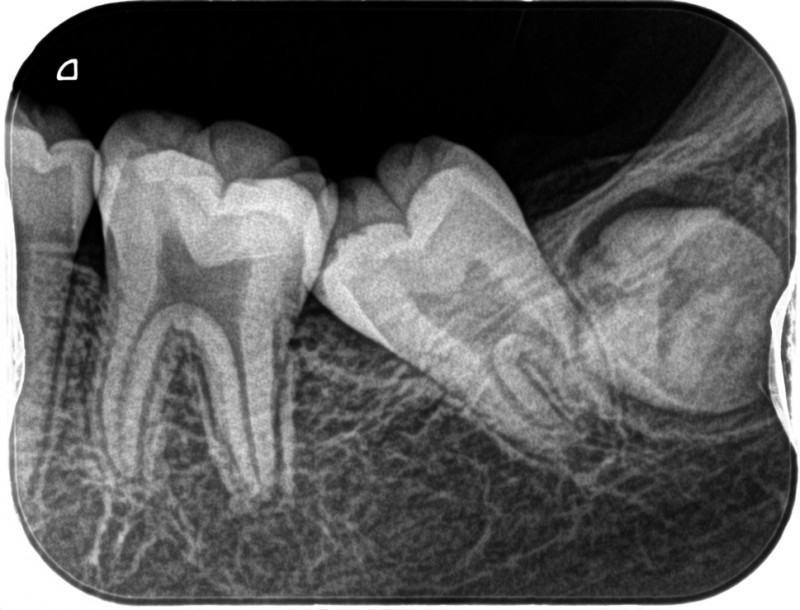

↑左下一番奥の歯(第二大臼歯)が、ひとつ前の歯(第一大臼歯)に引っかかって、萌出できない状態になっています。放置すると、引っかかったままの状態になります。親知らずが成長してくると、治すのも難しくなっていきます。

このようなケース、結構見かけます。

早期治療が大切です。